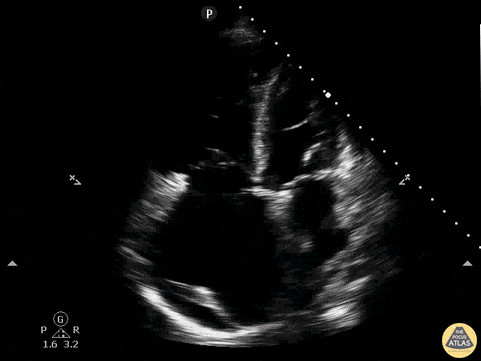

Right Ventricular Dysfunction - RV Dilation, Effusion, A4C

A patient presenting with acute onset undifferentiated shortness of breath. POCUS was used to narrow the differential. Parasternal short axis demonstrated flattening of the interventricular septum which pushes the left ventricle into the shape of the letter D. Known as the sonographic D-sign, it is correlated with significant right ventricular overload. This sign is not highly sensitive for PE, but can be 80-90% specific when found and associated with other signs of right ventricular strain. Also note on this study: moderate pericardial effusion, right ventricular dilation. Drs. Ronald Rivera, Elizabeth Hanson, Melanie Malloy - Emergency Medicine Residents Dr. Kelly Maurelus, Ultrasound Education Director Kings County/SUNY Downstate Emergency Medicine